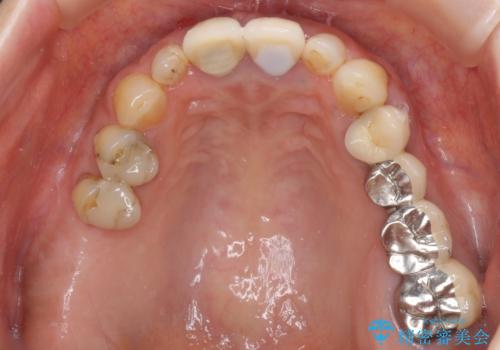

折れてしまった前歯 オールセラミックブリッジで自然な口元に

- 神経の抜いた歯が折れてしまい、痛みを感じて来院された患者様です。

折れてしまった歯は抜歯せざるを得ないため、抜歯と同時に仮歯を装着し、その後オールセラミックブリッジにて補綴することとしました。

折れた前歯を抜歯すると、歯肉が痩せてしまい、ブリッジの形態の審美性が失われることがあります。仮歯を調整することで審美回復が必要であるか判断しますが、今回は歯肉移植を行うことなく補綴治療を行いました。